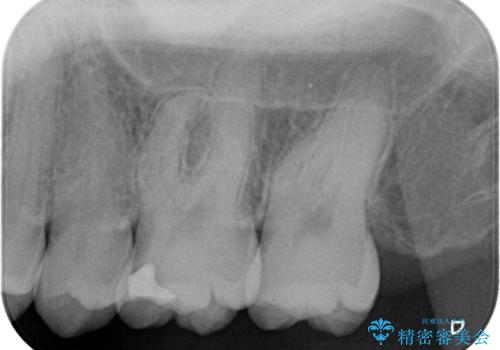

- クリーニング時に治療が必要な大きさの虫歯が見つかりました。

審美性と材料の安定性からセラミックでの修復を行うこととなりました。

う蝕を除去し、CRにて裏層をし、セラミックインレーにて修復しました。

ラバーダム防湿をした上で、接着しました。